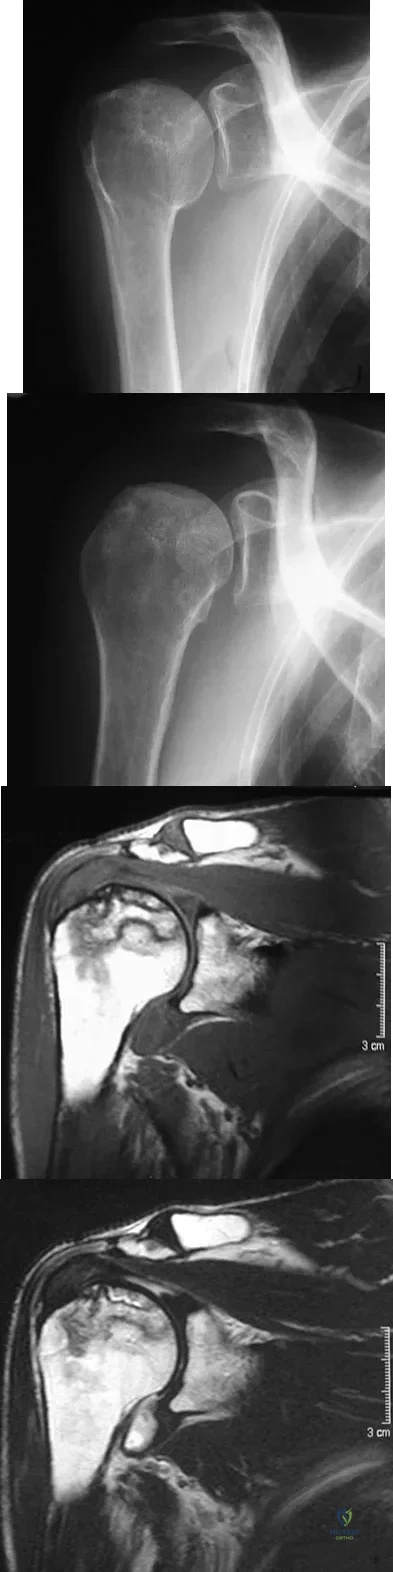

A 58-year-old woman with a history of severe asthma and long-term prednisone use reports a progression of chronic shoulder pain for the past 6 months. Radiographs and MRI scans are shown in Figures 30a through 30d. What is the most likely diagnosis?

Explanation

A 55-year-old woman with a 15-year history of systemic lupus erythematosus has had left shoulder pain for the past 3 months. She reports that the pain has grown progressively worse over the past few months, and her shoulder function is severely limited. She is presently being treated with azathioprine and has used corticosteroids in the past. AP and axillary radiographs are shown in Figures 19a and 19b, and MRI scans are shown in Figures 19c and 19d. Which of the following forms of management will yield the most predictable pain relief and return of shoulder function?

Explanation